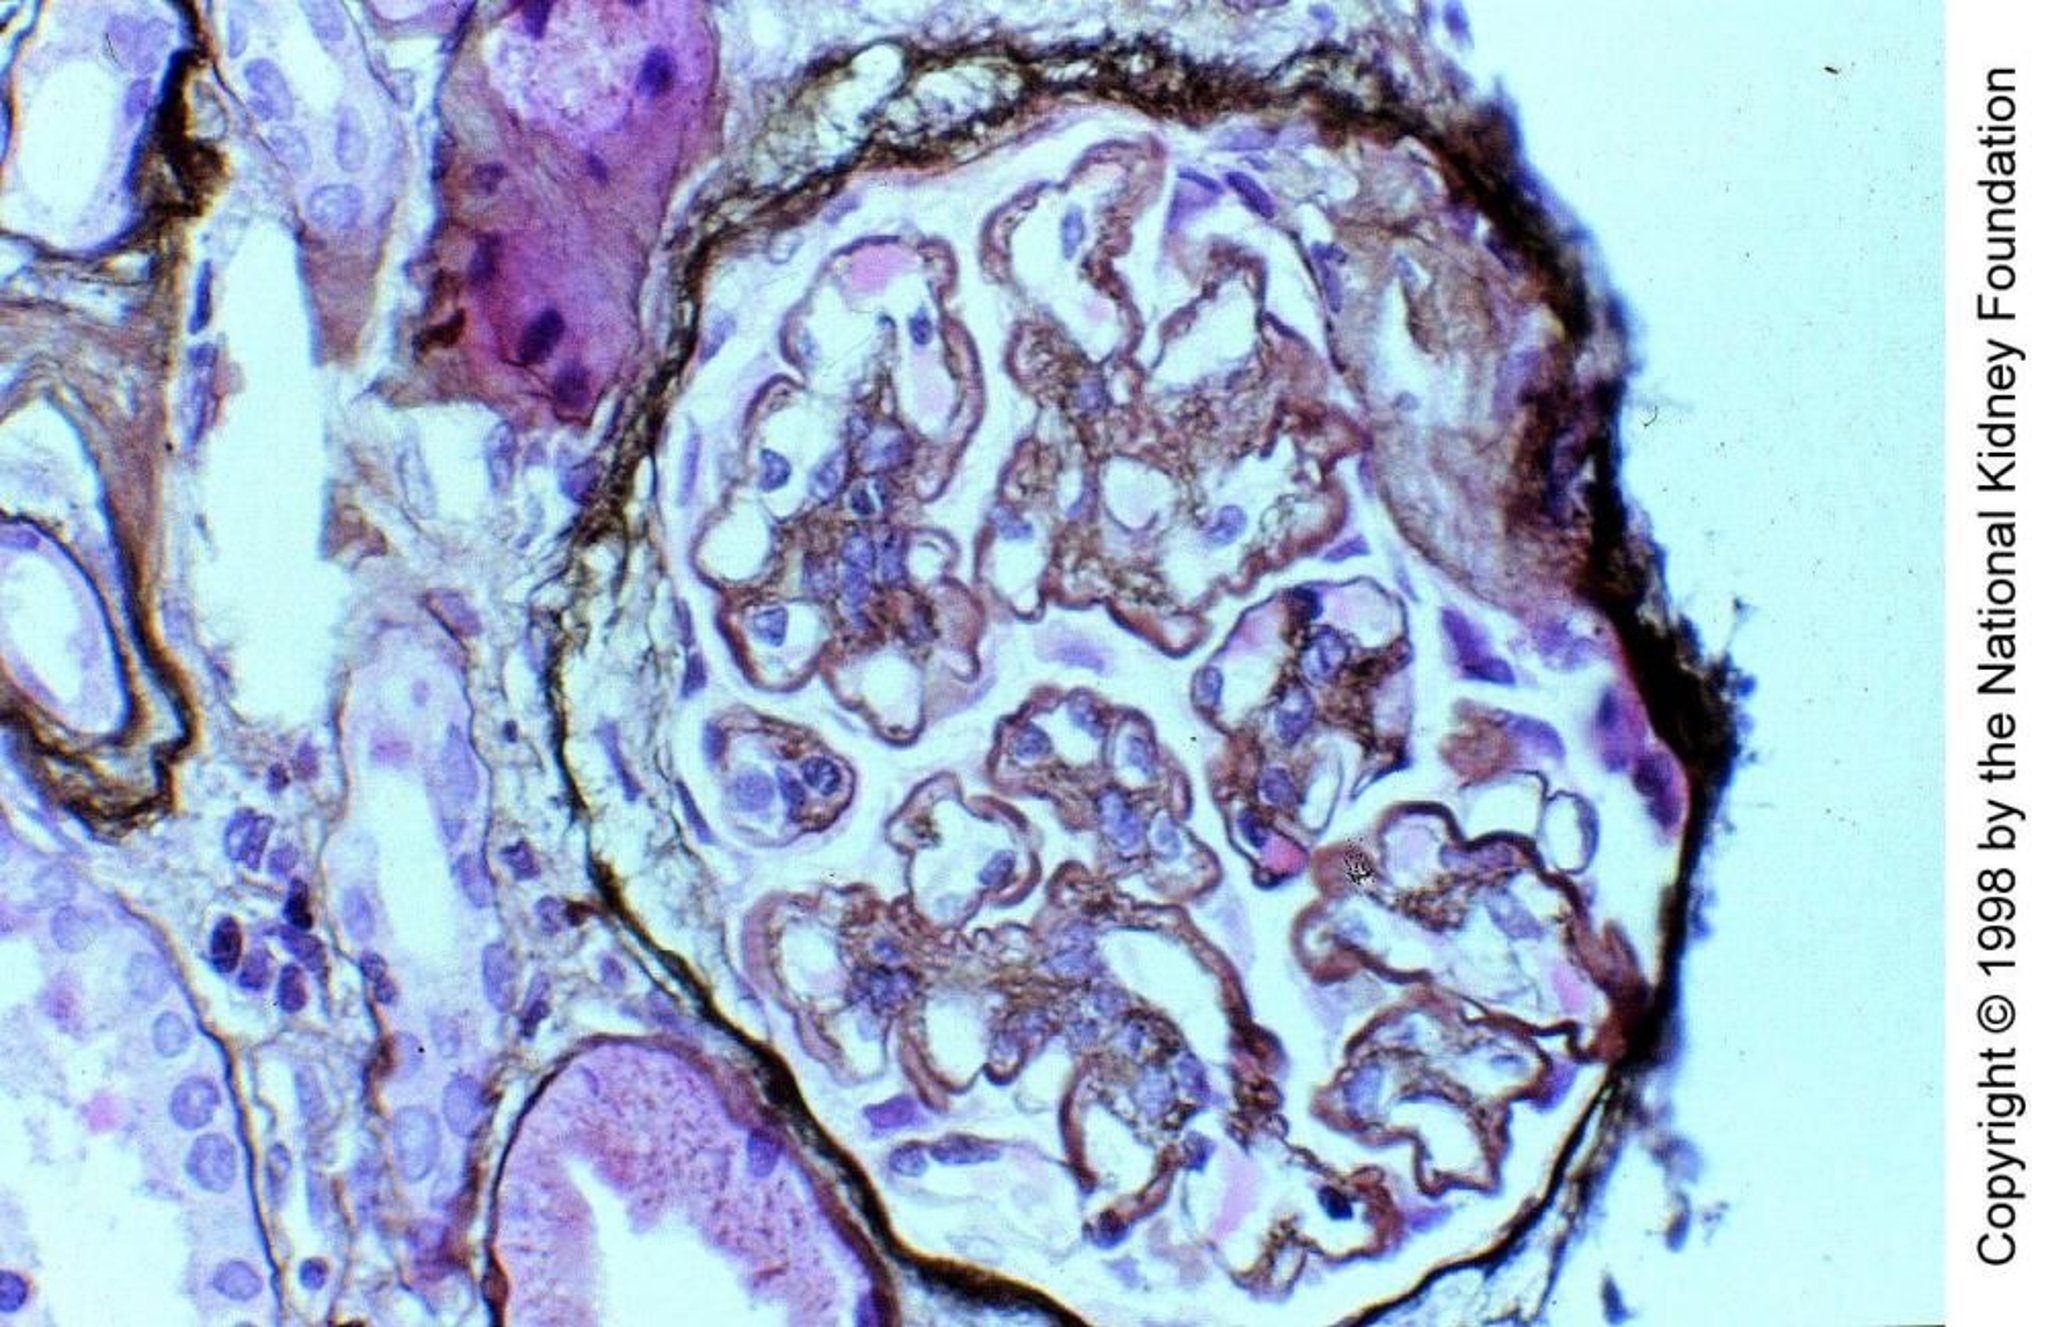

Glomerulonefrite membranoproliferativa, mediata dal complemento

Nella glomerulonefrite membranoproliferativa mediata dal complemento di tipo II, il fattore nefritico C3, un autoanticorpo IgG che funziona come la properidina clivando direttamente C3 in C3b, attiva il complemento attraverso la via alternativa all'interno delle pareti dei capillari glomerulari e del mesangio. I depositi di C3 sostituiscono parzialmente la lamina densa della membrana basale, conferendole un aspetto ispessito e caratteristico a nastro (colorazione all'argento di Jones, ×400).

Imagine fornita da Agnes Fogo, MD, and the American Journal of Kidney Diseases' Atlas of Renal Pathology (vedi www.ajkd.org).